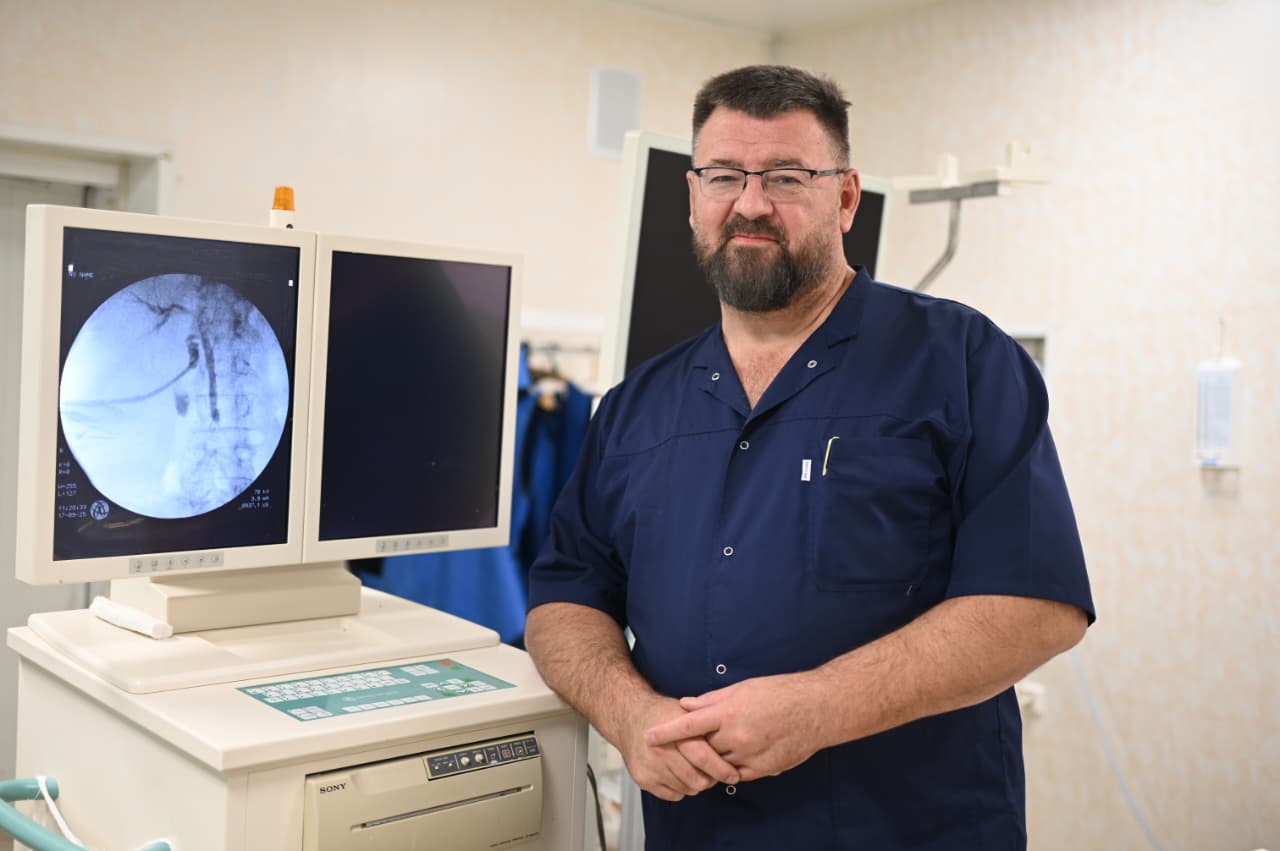

В Городской клинической больнице №14 Екатеринбурга апробировали новую медицинскую технологию — ультратонкий цифровой холедохоскоп SpyGlass. С помощью этого оборудования врачи провели малоинвазивную операцию 86-летней женщине с крупным камнем в желчных протоках, для которой традиционное хирургическое вмешательство было сопряжено с высокими рисками. Внедрение современных методик медицинской помощи пациентам в свердловских учреждениях здравоохранения соответствует задачам национального проекта «Продолжительная и активная жизнь».

«В стационар 86-летняя пациентка поступила с камнем размером 25х20 миллиметров в желчном протоке. В силу возраста, множества сопутствующих заболеваний и тяжести основной патологии выполнение полостной операции сопровождалось высоким риском. Использование чрескожного доступа в протоки обрекало женщину как минимум на 2,5 месяца ношения наружного дренажа, необходимости пить желчь, выполнять ежедневные перевязки», — рассказал заведующий отделением лучевой диагностики ГКБ №14 Алексей Ковалевский.

Бригада медиков провела операцию в два этапа. Сначала был обеспечен доступ к желчным протокам, затем с помощью холедохоскопа SpyGlass проведена холангиоскопия и выполнена контактная лазерная литотрипсия конкрементов с удалением осколков.

«Технология SpyGlass открывает новые возможности в лечении пациентов с высокой степенью операционного риска. Это пример того, как современное медицинское оборудование позволяет выполнять хирургические вмешательства у пациентов со сложным холедохолитиазом и с высокой степенью через естественные пути, минимизируя травматизм, боль и сроки восстановления. Мы надеемся активно развивать это направление в нашей больнице», — подчеркнул специалист учреждения здравоохранения.

Добавим, что SpyGlass (дословно «подзорная труба») — это ультратонкий эндоскоп, который проводится в желчные протоки через канал операционного дуоденоскопа, введённого в просвет двенадцатиперстной кишки. Технология обеспечивает прямой визуальный контроль, превращая диагностику в лечебную процедуру. Врач видит желчные протоки изнутри в высоком качестве, далее также под визуальным контролем крупные камни дробятся лазером на мелкие фрагменты, которые извлекаются наружу. Визуализация просвета желчных протоков позволяет также прицельно забирать образцы тканей для исследования при подозрении на опухоль.